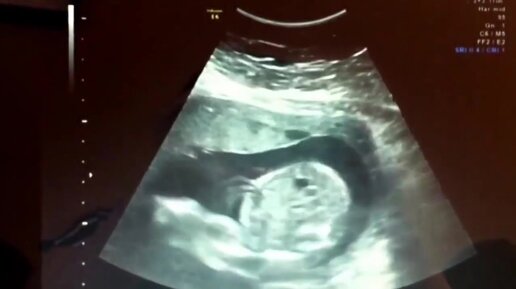

УЗИ на 24 неделе беременности

Медицинский женский центр